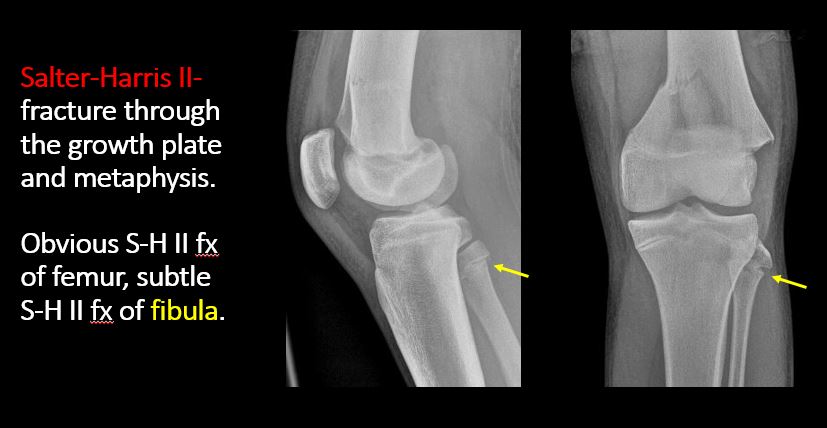

There is a fracture through the physis which then extends into the metaphysis with or without angulation or displacement (S-H II). [Yes/No]